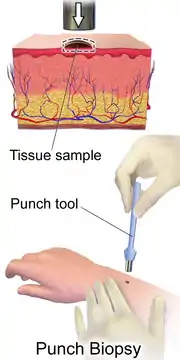

The diagnosis of T-cell lymphoma varies largely between the subtypes. Some subtypes like anaplastic large-cell lymphoma have an exceptional diagnostic rate however,[4] for a majority of T-cell lymphoma subtypes the diagnosis is often flawed due to the difficulty to culture damaged lymphoma cells and the overall low frequency of cases compared to other Non-Hodgkin lymphoma.[6] The current and most accurate diagnosis used across most subtypes is a biopsy in which fresh tissue that is suspected to be affected by the lymphoma is collected from the patient to be closely examined by pathology laboratories.[2] Other diagnostic methods are specific to the type of T-cell lymphoma, physical examination of skin or lymph nodes is common for cutaneous subtypes of T-cell lymphoma whilst others may be diagnosed using blood tests. Series of scans such as CT scan, MRI, ultrasounds, and even X-rays may also be used for diagnostic purposes.[1]